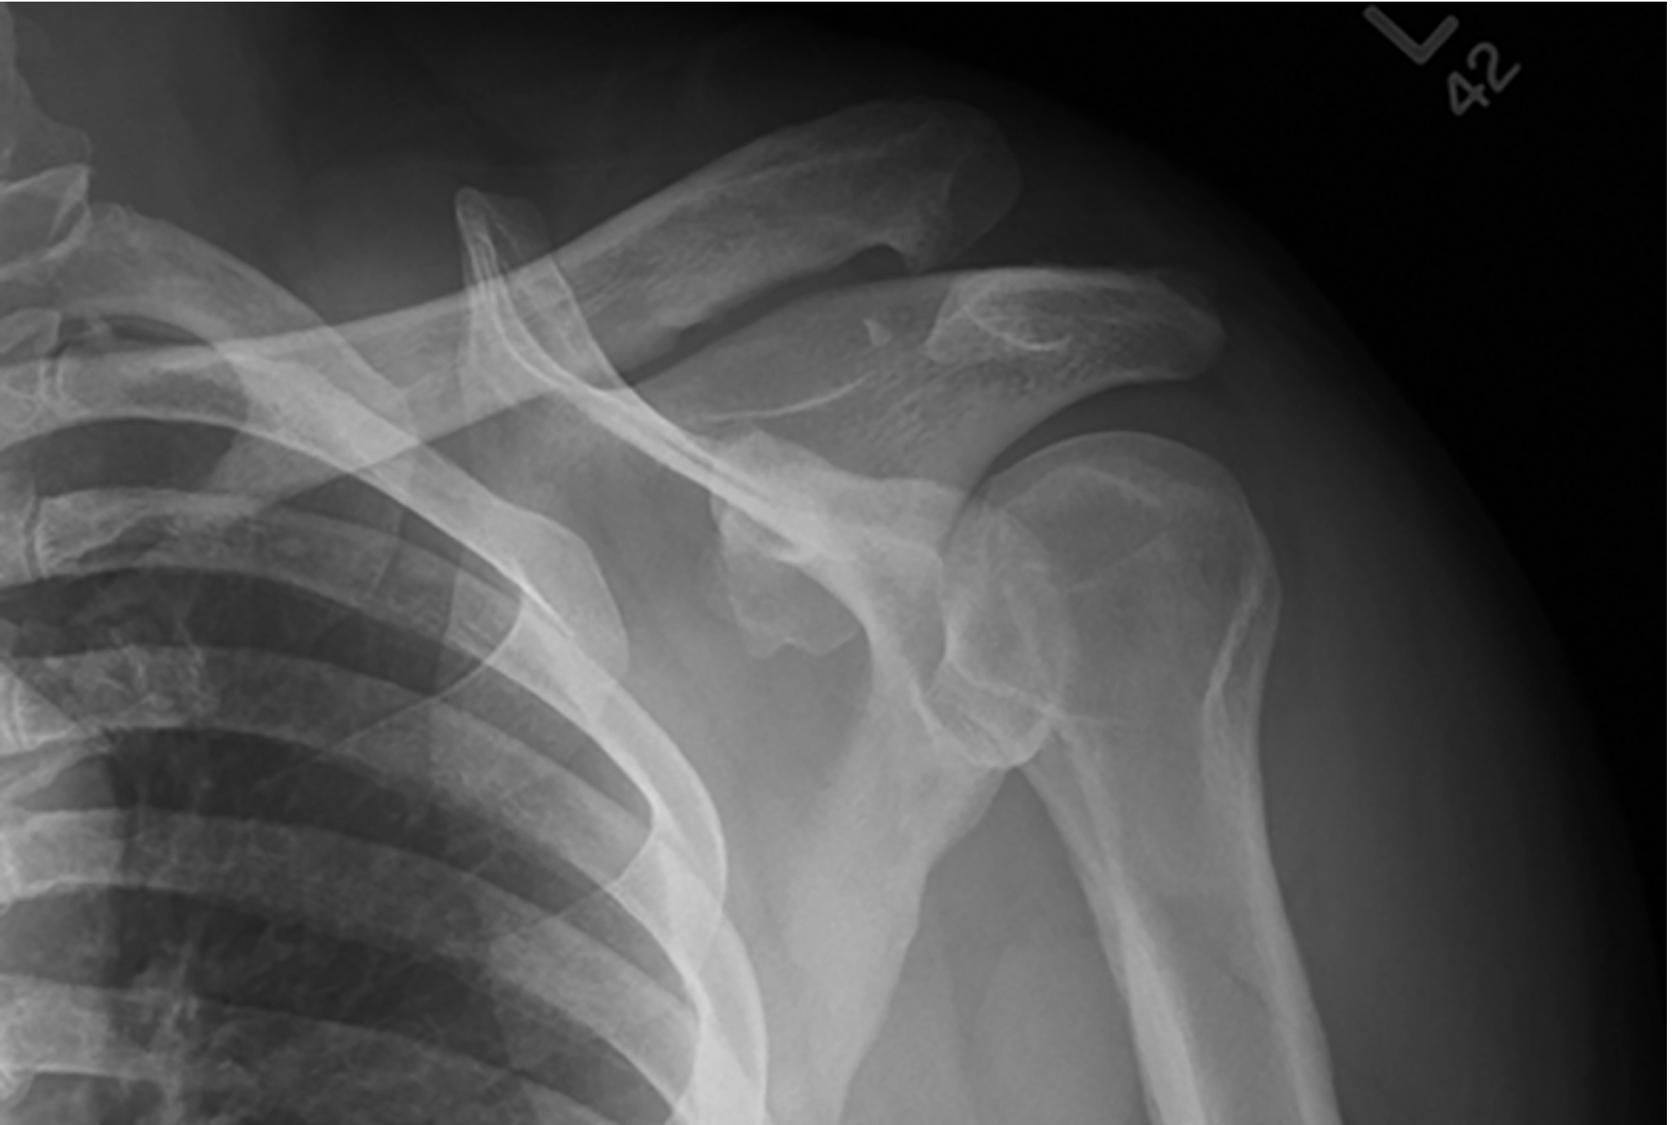

An axillary or modified axillary view is an essential part of the radiographic series ( Fig. 9.4 ).

Fig. 9.4

Confirm that the humeral head is not impacted onto the glenoid (known as a Hill-Sachs lesion) before attempting a reduction (see Fig. 9.4 ). Standard reduction maneuvers can result in a head-splitting fracture.